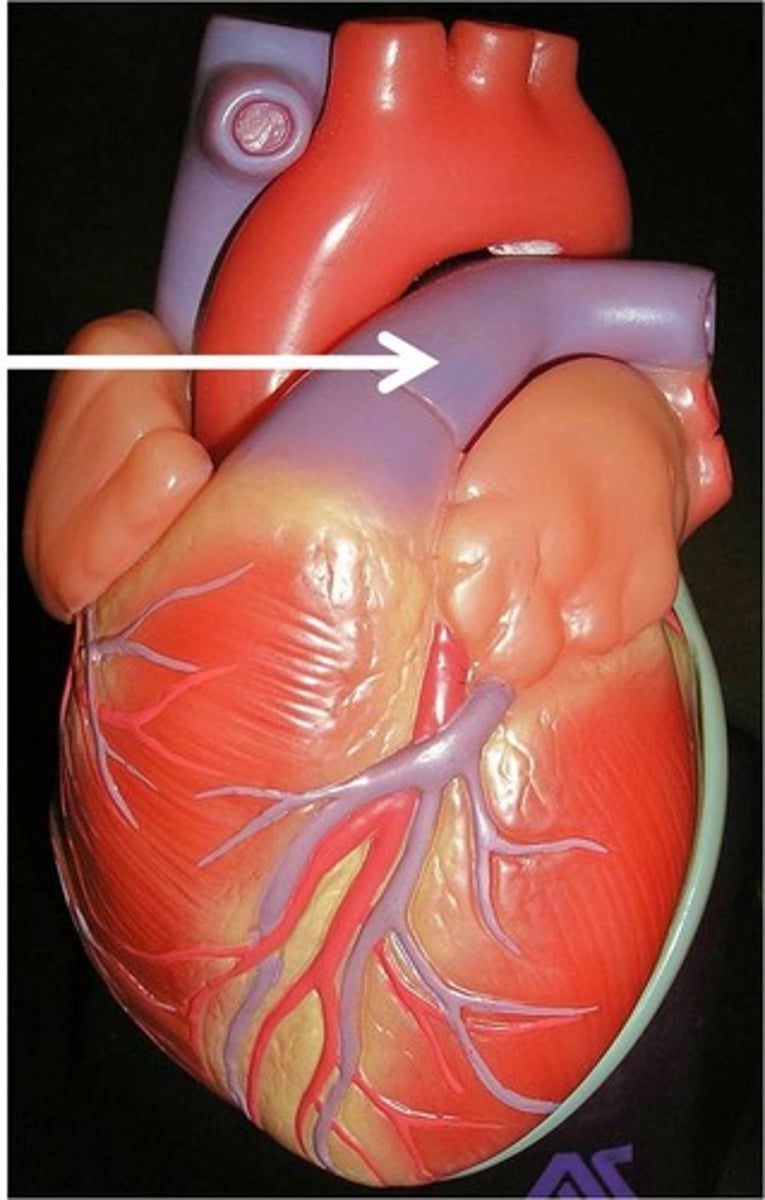

left auricle